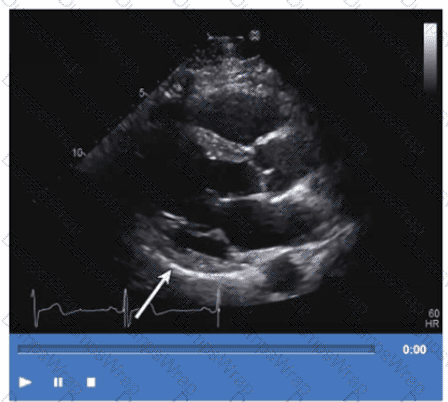

Which step is next in further evaluation of the abnormality shown in this video?

CExplanation:

Comprehensive and Detailed Explanation From Exact Extract:

The video suggests an atrial septal abnormality possibly a patent foramen ovale or interatrial shunt. To evaluate for right-to-left shunting across an atrial septal defect, the administration of agitated saline contrast with a Valsalva maneuver is the next best step.

Valsalva increases right atrial pressure transiently, promoting transient right-to-left shunting, making microbubbles visible in the left atrium if a shunt is present. Administration without Valsalva reduces sensitivity. The choice of arm vein (right or left) is less critical.

This diagnostic technique is well described in ASE adult congenital heart disease guidelines and echocardiography contrast protocols【12:ASE Contrast Echocardiography Guidelines†p.190-195】【16:Textbook of Clinical Echocardiography, 6e†p.575-580】.